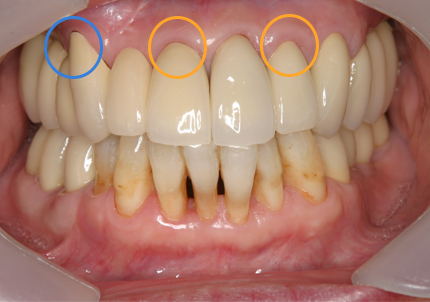

1.初診時口腔内写真(2018年10月)

1.初診時口腔内写真(2014年6月)

受傷前の口腔内写真(2012年8月6日 前歯部治療終了時写真)